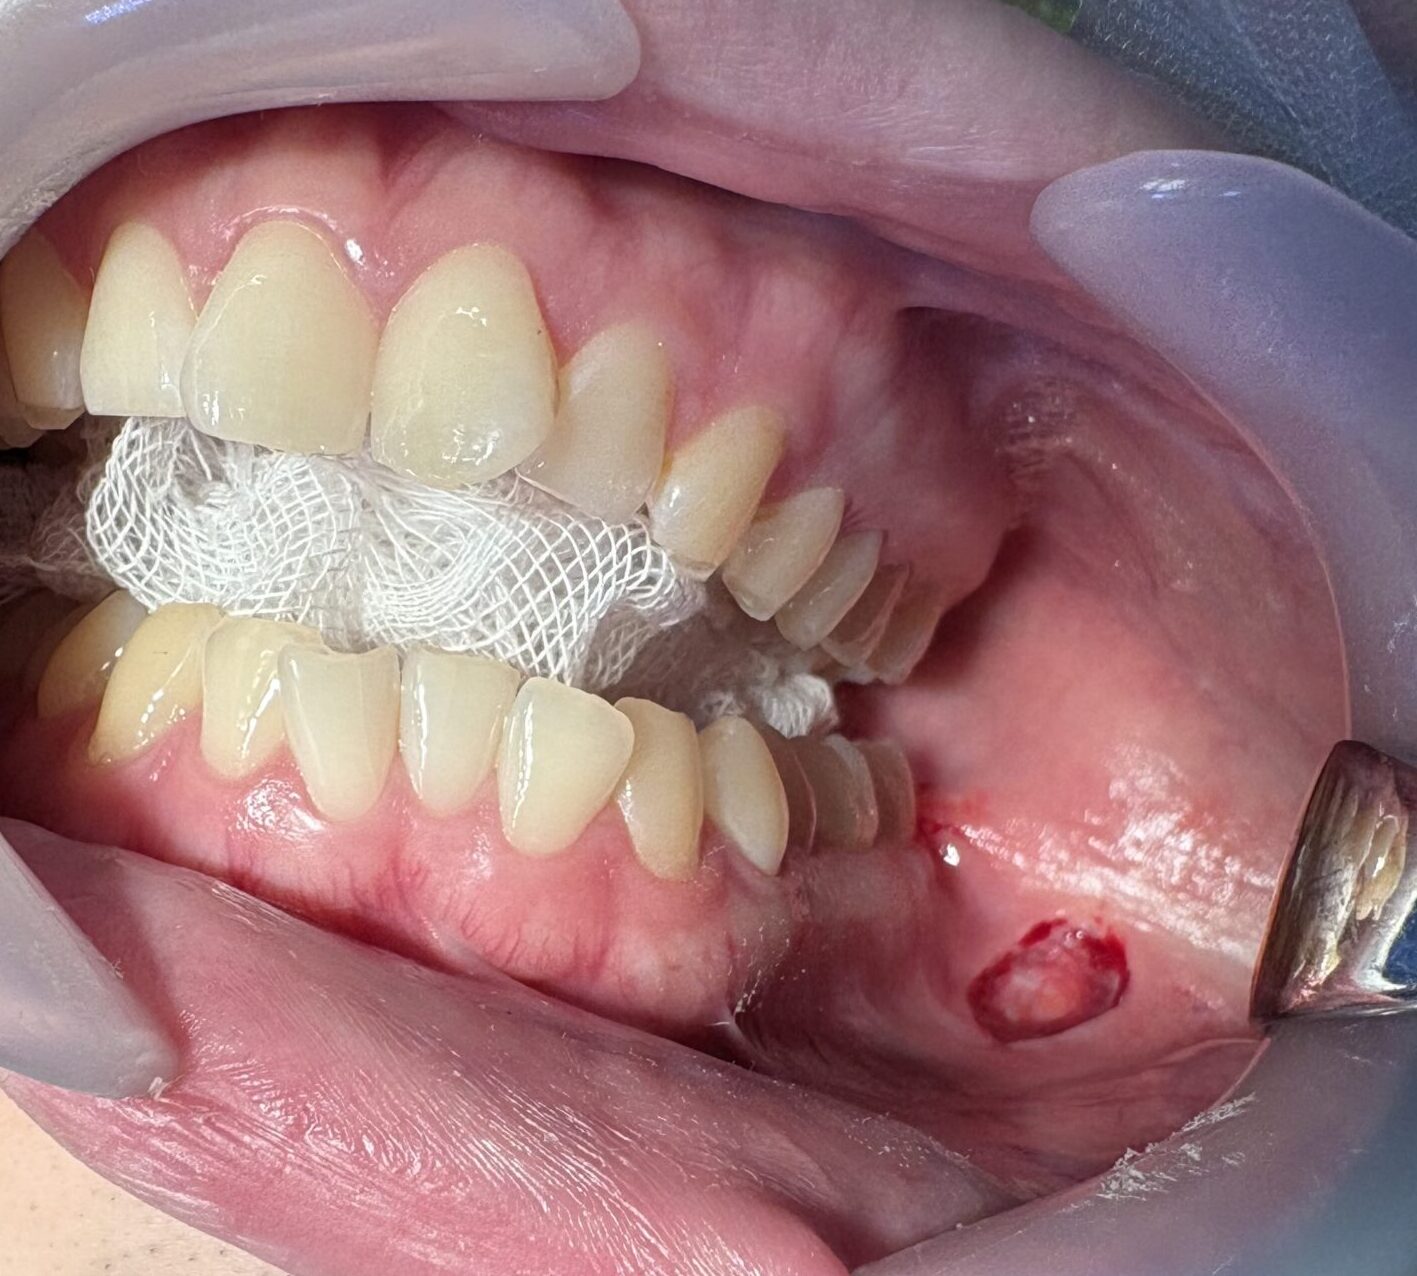

患者様の左(画像の右側)に小さな切開をします。この小さな切開から手術を行います。